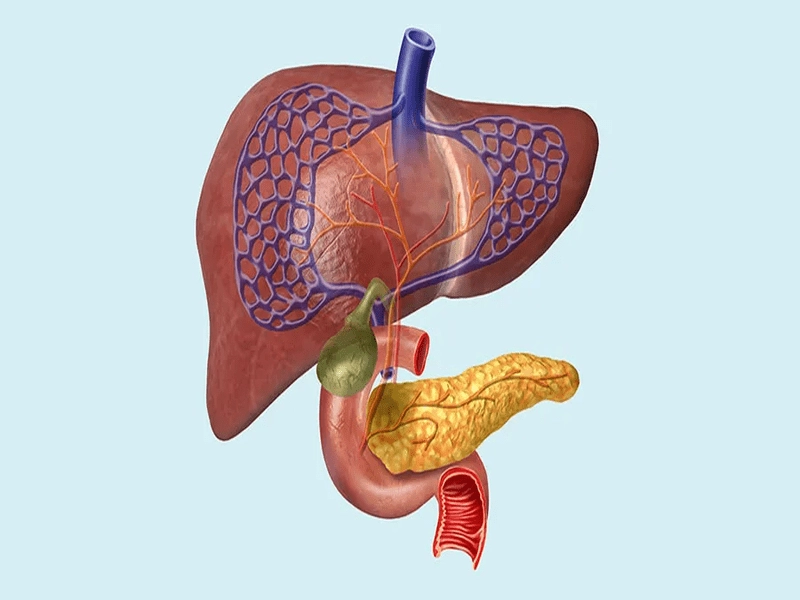

هپاتوبیلیاری به مجموعهای از اندامها و ساختارهای حیاتی در بدن اشاره دارد که شامل کبد، کیسه صفرا، مجاری صفراوی و پانکراس میشود. این سیستم پیچیده مسئولیتهای مهمی از جمله تولید صفرا، هضم چربیها، تنظیم قند خون و تولید آنزیمهای گوارشی را بر عهده دارد. هرگونه اختلال در عملکرد این اندامها میتواند به مشکلات جدی سلامتی منجر شود.

جراحی هپاتوبیلیاری به مجموعهای از روشهای جراحی گفته میشود که برای درمان بیماریها و اختلالات مربوط به سیستم هپاتوبیلیاری انجام میگیرد. این جراحیها میتوانند شامل برداشتن تومورها، ترمیم آسیبها، باز کردن انسدادها و یا پیوند اعضا باشند. به دلیل پیچیدگی و حساسیت این اندامها، جراحیهای هپاتوبیلیاری معمولاً توسط جراحان متخصص و با تجربه انجام میشود.